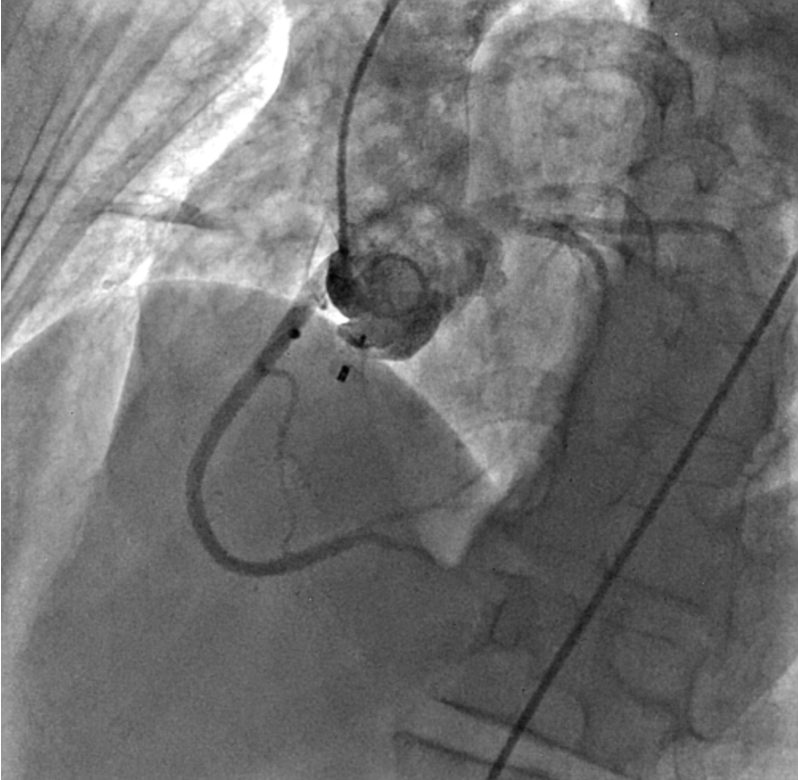

Ultrasound-guided dual access was completed, with a right femoral arterial as well as a venous approach. An aortogram was performed using the arterial approach, following introduction of a pigtail catheter at the level of the non-coronary aortic sinus, which showed a connection between the right atrium and the non-coronary aortic sinus (Figure 1, Video 1).

Figure 1. An aortogram revealing a communication between the right atrium and the non-coronary sinus of Valsalva (white arrow).